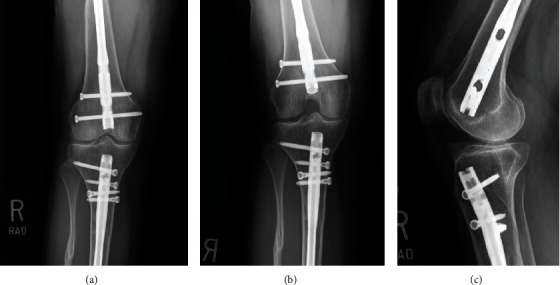

异位骨化是软组织内的异位片状骨形成,可导致严重的功能限制。异位骨化有多种潜在病因,包括肌肉骨骼创伤和创伤性脑损伤。膝关节内 HO 比较罕见,通常位于十字韧带内。我们报告了一例 24 岁女性的病例,她在一次车祸中多处下肢骨折,两年半后出现右膝关节疼痛加重和膝关节伸展受限。体格检查显示膝关节前部疼痛、伸展受限,并可触及髌下突出。影像学检查显示髌骨后肌腱、胫骨前平台近端关节内骨赘。使用70°关节镜进行诊断性关节镜检查,发现胫骨前平台近端有HO,在直视下使用高速毛刺将其切除。在三个月的随访中,患者仍无症状,并恢复了运动。髌后肌腱、关节内膝关节前HO是一种罕见的临床病症,但可以在70°关节镜直视下成功安全地进行切除。

Heterotopic ossification is ectopic lamellar bone formation within soft tissue and can result in significant functional limitations. There are multiple underlying etiologies of HO including musculoskeletal trauma and traumatic brain injury. Intra-articular HO of the knee is rare and is typically located within the cruciate ligaments. We report a case of a 24-year-old female who presented with worsening right knee pain and limited knee extension two and a half years after a motor vehicle crash with multiple lower extremity fractures. Physical examination of the knee revealed anterior pain, limited extension, and a palpable infrapatellar prominence. Imaging showed a retropatellar tendon, intra-articular excrescence of bone proximal to the anterior tibial plateau. Diagnostic arthroscopy with a 70° arthroscope identified HO at the proximal anterior tibial plateau, which was excised with a high-speed burr under direct visualization. At the three-month follow-up, the patient remained asymptomatic and returned to sport. Retropatellar tendon, intra-articular anterior knee HO is a rare but debilitating clinical entity that can be successfully and safely managed with excision under direct visualization using a 70° arthroscope.